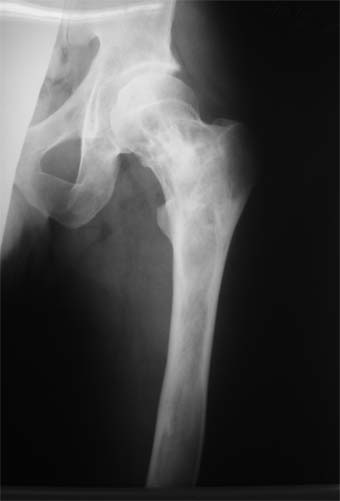

Коллеги!Пациент Д., 35 лет, В 1985 году был поставлен диагноз гемигипоплазия правой нижней конечности. Укорочение 5 см, в 1987 году остеотомия правого бедра, аппарат 4 месяца, удлинили на 2 см из-за нагноения спиц аппарат сняли. В настоящее время Жалобы на дискомфорт, тяжесть в левом бедре, голени при длительной ходьбе, при длительном лежании на левом бедре. Эти жалобы беспокоят втечение 5-6 лет. В 1999 году выявили "изменения" (со слов больного, выписки нет на руках) бедренной кости и костей голени слева. Тогда же предложили в ЦИТО срочно делать какую-то операцию. При осмотре: Правая нижняя конечность. Имеются рубцы на правом бедре по наружной и внутренней поверхностям. Ограничения движений в коленном суставе нет. Кровоснабжение, иннервация сохранены. Левая нижняя конечность. Левое бедро увеличено в объеме, при пальпации пальпируется бедренная кость большего диаметра по сравнению с левым бедром. Пальпация безболезненна. Голень обычной формы. Объем движений в суставах полный. Кровоснабжение, иннервация сохранены. Имеется разница в длине конечностей правая короче на 4-5 см за счет бедра и голени. В приложении вид больного и рентгенограммы бедра 2001 год и 2005 год. Что бы это могло быть? О чем можно думать? Онкология? С уважением Коробушкин Глеб Владимирович Российский государственный медицинский университет кафедра травматологии, ортопедии и ВПХ, доцент

Остеосклеротическая стадия болезни Педжета. Имею двух подобных больных по 15 -20 лет наблюдения. В острой стадии - текли как классическая саркома. "За" - все (рентген+биопсия+клиника) - отправили хоронить, а в результате живы и имеют рентген-картинку похожую Вашей. Поройтесь в минеральном обмене и в почках. Удлинять подобные кости опасно. Можно -биопсию на всякий случай (из зоны склероза и зоны пороза).

В настоящее время имеется умеренный рубцовый процесс правого бедра не мешающий на объем движений в суставах. В коленном суставе слева бедро обычное, голень - булавовидное утолщение проксимального конца большеберцовой кости. На рентгенограммах тотальное поражение кости с увлечением в процесс проксимального эпиметафиза, поражение характерно для болезни Campanatsehi

У больного полиоссальноая форма фиброзной дисплазии с поражение левой бедренной и большеберцовой кости. На рентгенограммах - тотальное разрастание и остончение кортикального слоя. Имеется удлинение левой нижней конечности на 2,5-3 см за счет голени. Больному показано оперативное лечение левой большеберцовой кости.